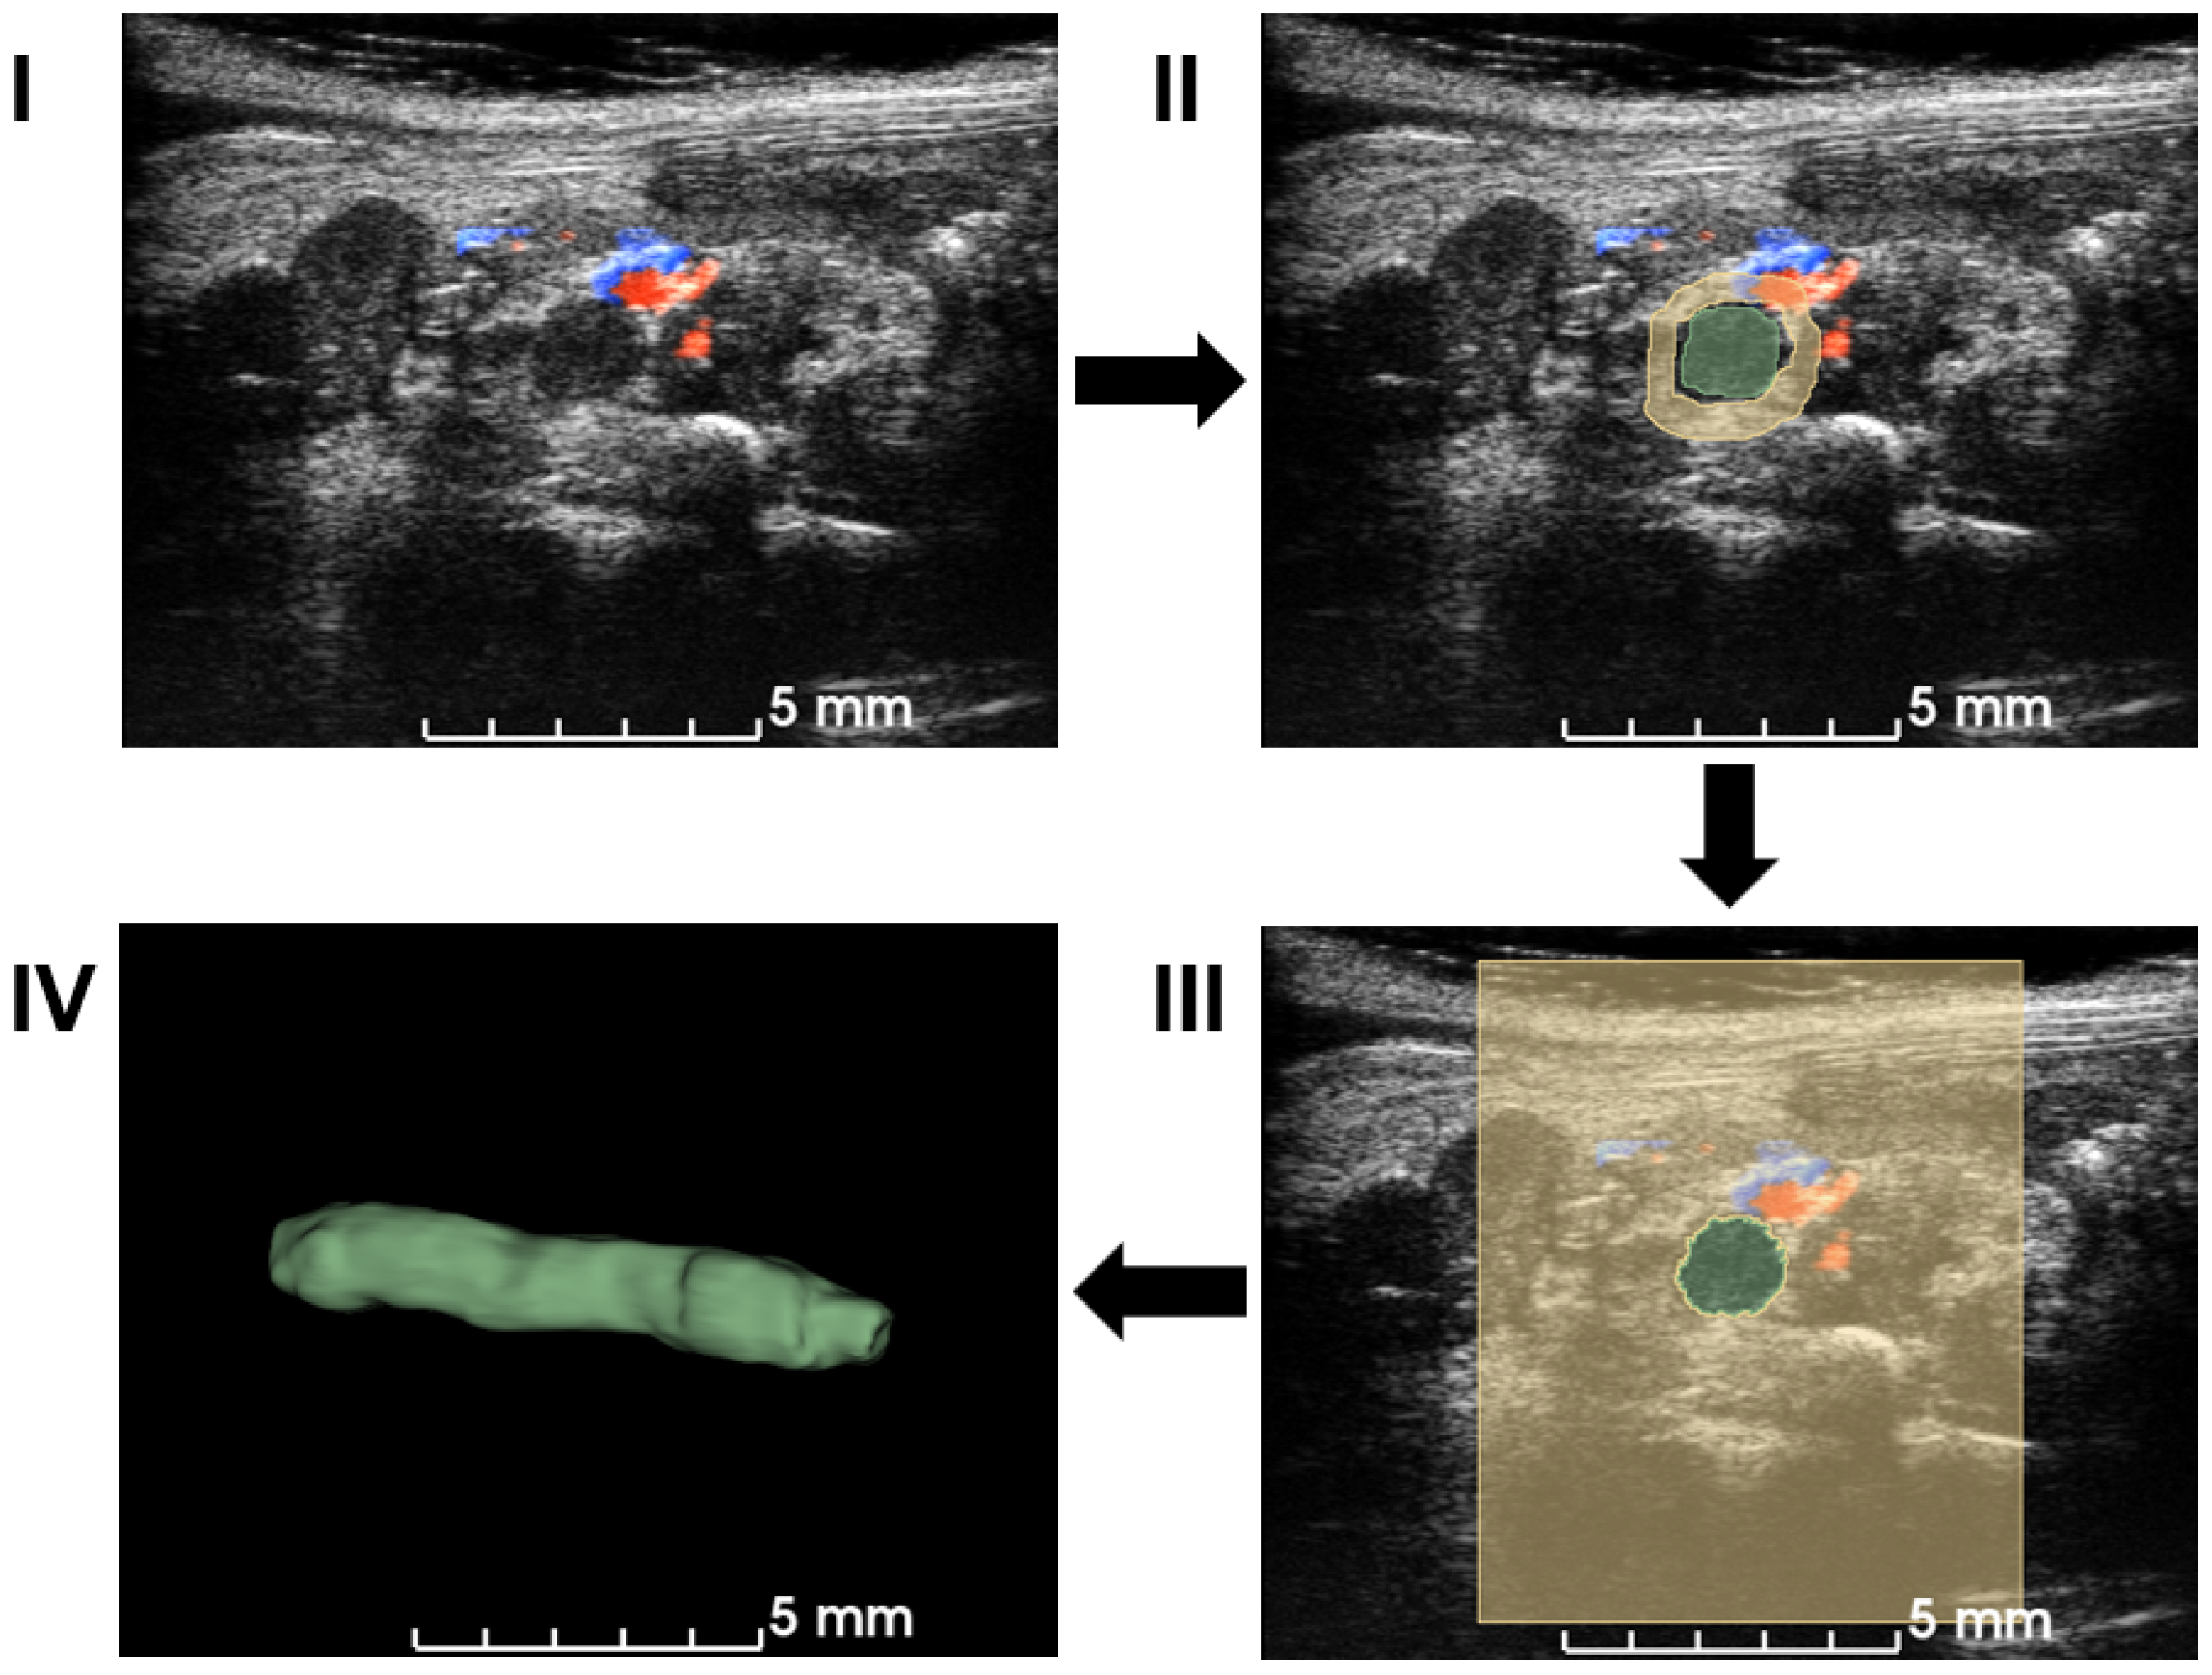

The workflow employed a semiautomatic GrowCut segmentation workflow [27], as illustrated in Figure 2. Volumetric data in the imaging system were exported to a PC and loaded into 3D slicer software (Version 5.0.3) for image analysis [28]. Blood clots and background in a few slices in each direction (X–Z, Y–Z, and X–Y planes) were manually annotated, which was supervised by an expert surgeon. The existence of the blood clot was based on the static texture and Doppler blood flow signals. After accumulating more than 30 annotations, a growing-from-seeds algorithm was run on a 3D slicer to segment the volume of the 3D blood clot [27]. After smoothing the boundary to the volume of 3D blood clots provided in the software, the volume of the blood clots was measured as a quantification metric.

Figure 2. Workflow of the semiautomatic 3D segmentation. First, ultrasound volume is loaded into 3D slicer (I). Manual segmentation is performed on multiple slices and angles based on B-mode signal density and Doppler blood flow signal in (II). A seeding algorithm is run and the results are shown in a 2D view (III). Modifications are applied to extract a 3D volume of a blood clot in (IV). After the segmentation, the volume of the blood clot is calculated for quantification.